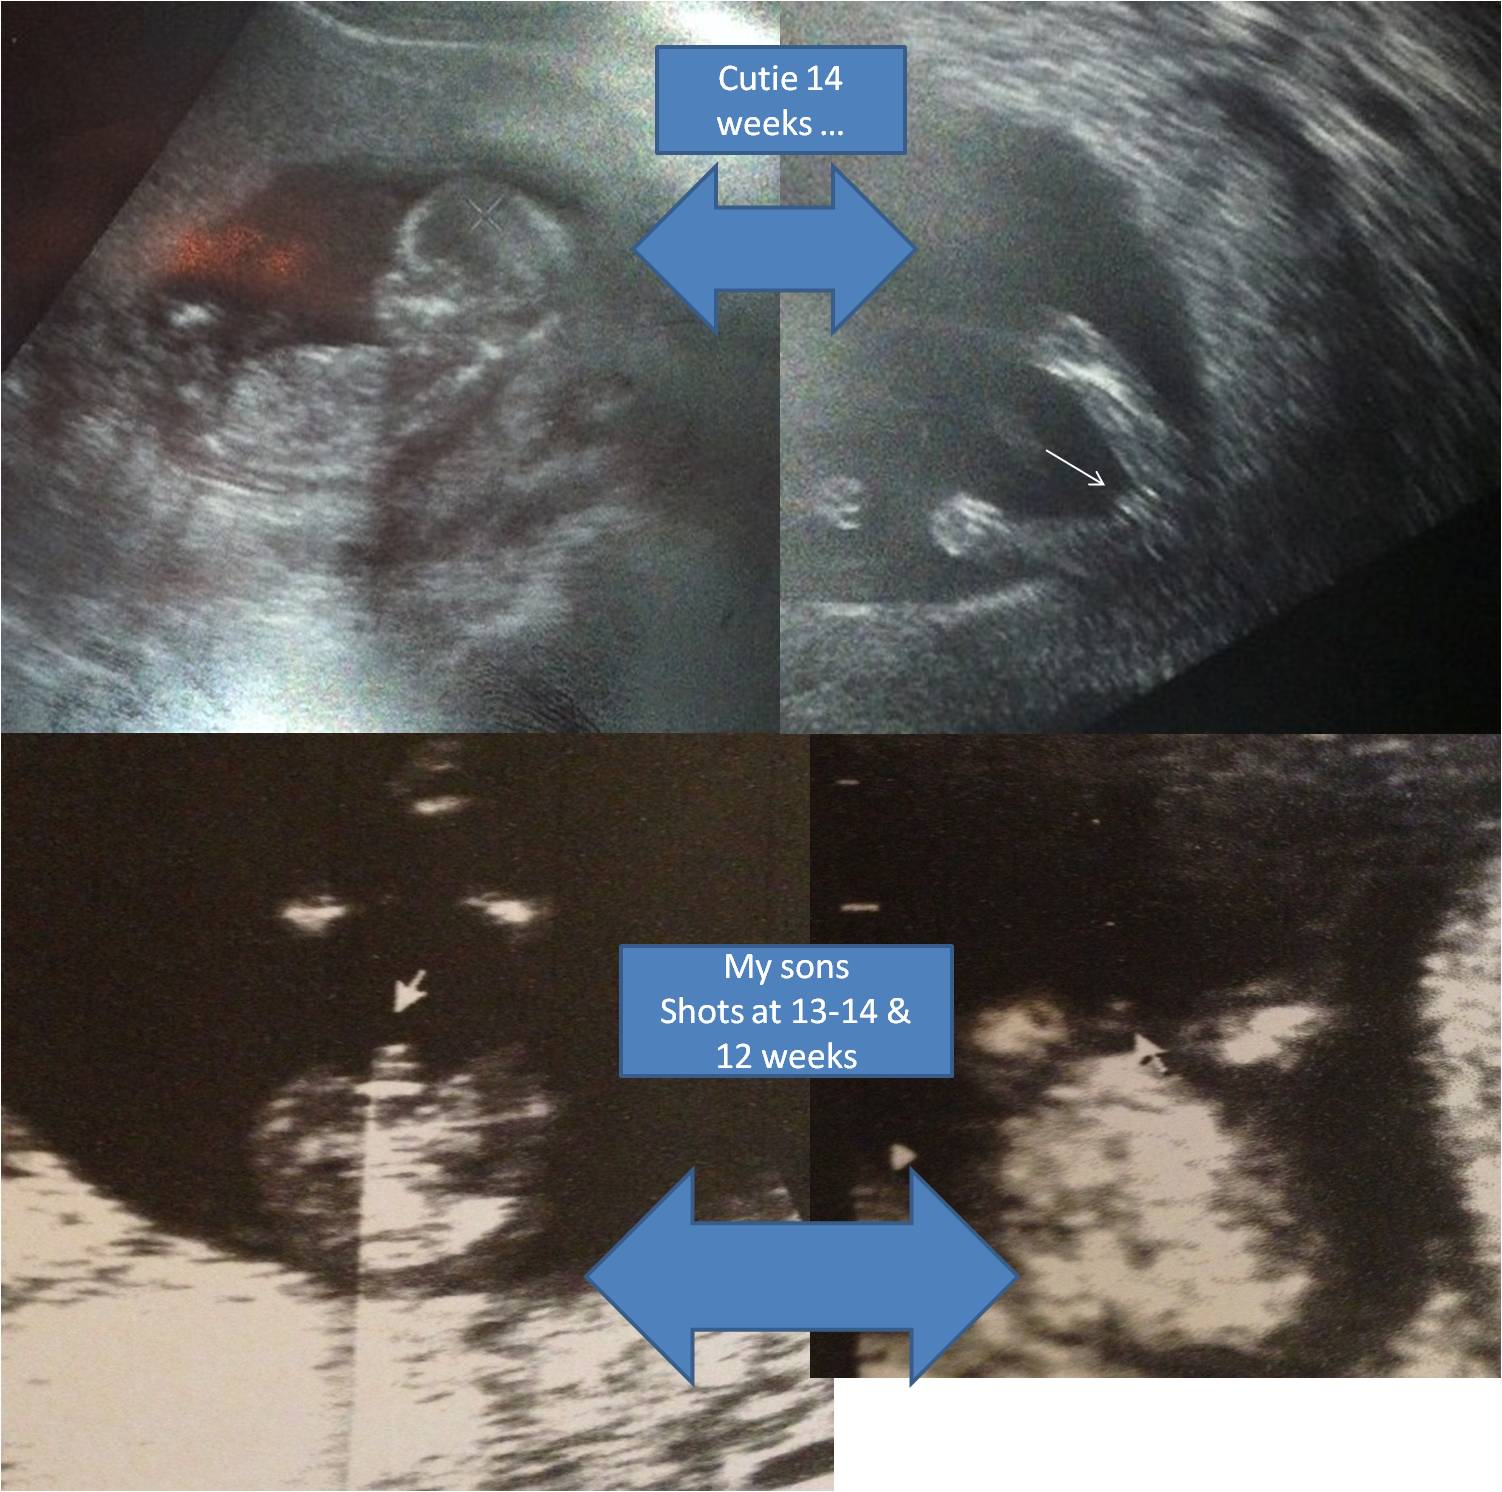

This is one of the shots we got from our 12w3d ultrasound for the NT, what are your thoughts, is it a boy or a girl? Thanks

You can compare with my boys at the NT scans ...

On another forum, there are people who are 100 sure they are having boys or girls. See with my son i never got a shot like that to compare it to. Thanks Ladies for the responses. Any of you done with peek a boo gender. outside your obs office where they tell you the gender at 14 weeks or 15 weeks?